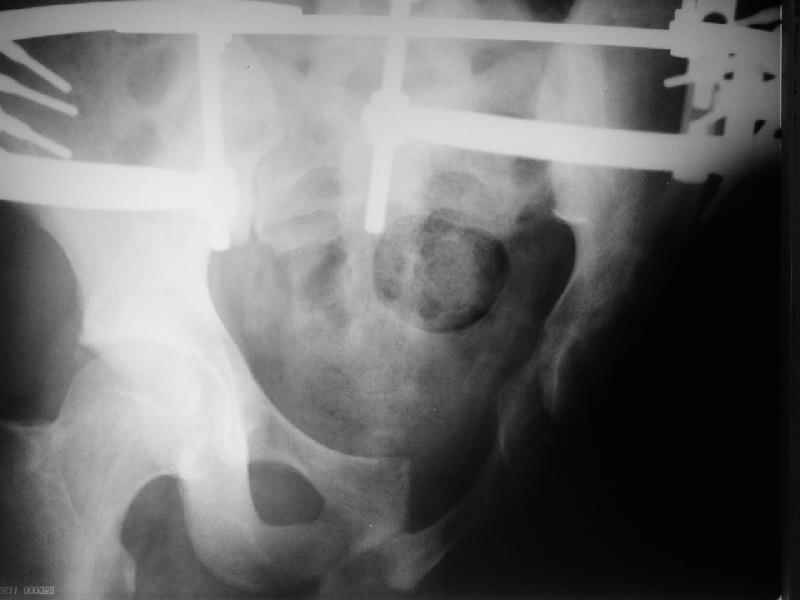

Уважаемые коллеги, в нашу клинику поступил молодой человек (25 лет),получивший травму в октябре 2003. До настоящего времени находился на лечении в другом лечебном учреждении, где пластически закрывали дефект (наша бригада на выезде накладывала аппарат). Сейчас аппарат демонтирован, можно было бы заняться протезированием, но после консультации протезиста из нашего ортопедического предприятия, оказалось, что сделать протез в данном случае не представляется возможным, поскольку нет опыта протезирования при отсутствии седалищной кости и опорной кожи (предлагается малофункциональная конструкция годов 60-х). Подскажите, как можно помочь пациенту, у нас или за рубежом. Травма производственная, с оплатой проблем быть не должно.

Уважаемый доктор Салаватов! Мы получили информацию о пациенте с отрывом левой нижней конечности и повреждениями области таза.

Отсутствие седалищной кости и грубые рубцовые деформации кожных покровов делает так называемую культю неопороспособной. Больному необходимо провести подготовку к протезированию комплексного характера, включая возможные хирургические вмешательства, например, проведение кожной пластики по уменьшению рубцового дефекта по методу

ФЦЭРИ, после чего больной будет протезирован с использованием разработанных нами технологий. Для оформления вызова больного отделение фонда социального страхования Вашего региона должно выслать в наш адрес гарантийное письмо на оплату лечения и протезирования.